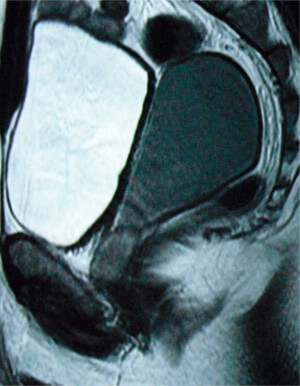

Mullerian cyst :

The mullerian duct cyst is a congenital condition represents remnant of the caudal ends of the fused müllerian duct, a structure that typically regresses in time. These cysts are typically located in the midline, behind the bladder, originating in the region urinary passage just below the level of prostate connected by a thin stalk. It is not associated with other congenital abnormalities of the urinary tract. The cystic fluid is devoid of sperms, and may be thick tenacious or sometimes blood stained. Rarely stones may occur within these cysts. It is common between 20 to 40 years.

The clinical presentation is varied, including urinary frequency, urgency, dysuria, urinary obstruction, hematuria, and pelvic pain. Digital rectal examination may reveal a midline mass superior to the prostate gland. Transrectal ultrasound and MRI will confirm the diagnosis.

These large cysts can be removed by laparoscopic surgery.